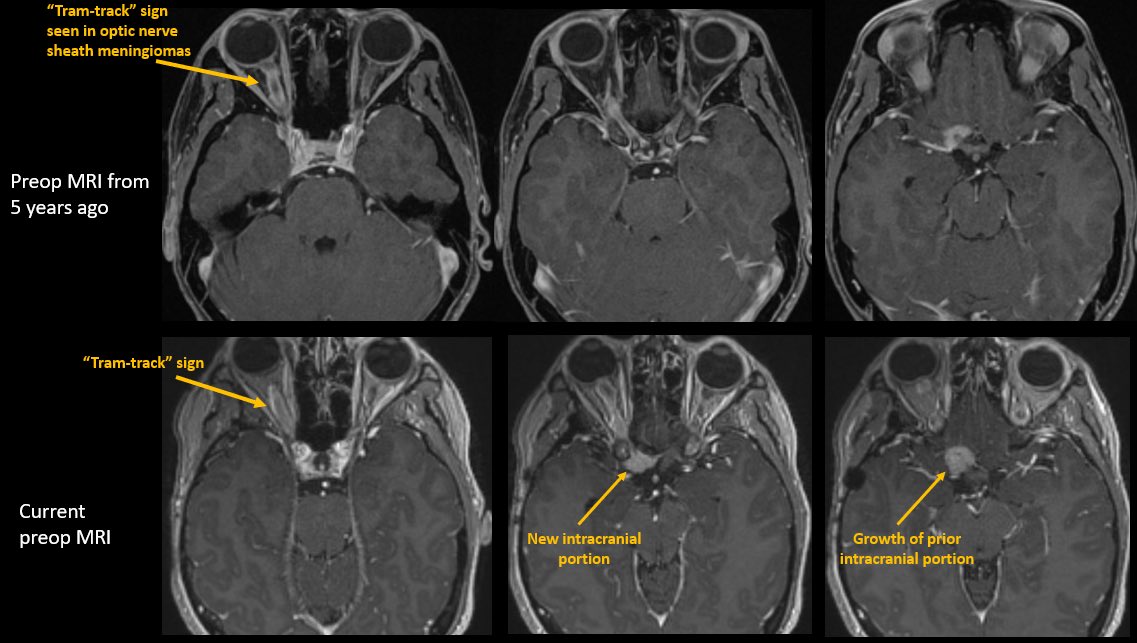

How would you manage this 42F w/ intracranial recurrence of optic nerve sheath meningioma initially biopsied at OSH 5 yrs ago. R eye blind, L 20/20, EOMI. Observation? Radiation? If surgery, approach/extent of resection? #Neurosurgery #MedEd #MedTwitter @EvaWuMD @TheJNS @WFNSHQ